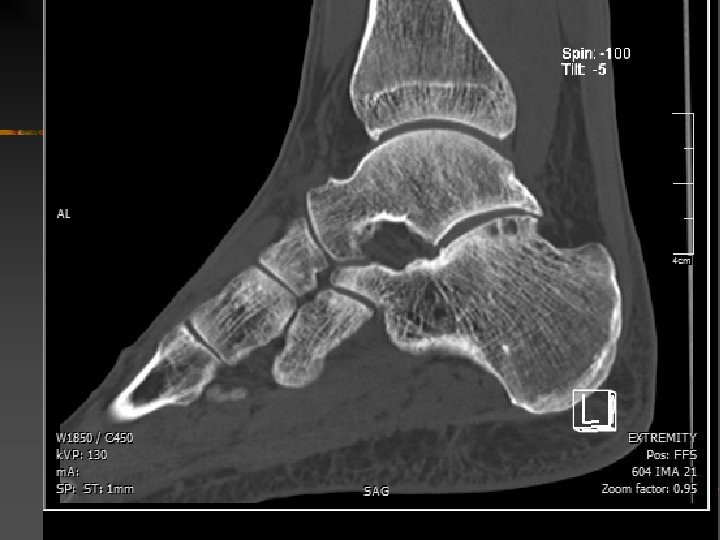

SCP : Rappel anatomique Les os

SCP : Rappel anatomique n Les os Processus postéro-latéral du talus (queue de l’astragale, proc. de Stieda) -Parfois volumineux -Parfois « os trigone » -Enthèse lig. talo-fib. post. et lig. talo-calc. post. -Parfois face inf. proc. lat. voire de OT forme artic. avec le calca

SCP : Rappel anatomique n Les os : L’os trigone

SCP : Rappel anatomique n Les os Processus postéro-latéral du talus : Os trigone - appar. noyau d’ossification 2 aire entre 7 et 13 ans - fusion au noyau ossif. 1 aire en +/- 1 an (10 ans chez fille ; 13 ans chez garçon) - pas de fusion chez environ 10% pop. sédentaire (…jusqu’à 80% ds série footballeur) - bilatéral ds 1, 4 % des cas - forme alors une synchondrose avec le talus - parfois bi ou multipartite… - taille habituelle <10 mm - Etiologie : - excès de traction par enthèse lig. (talo-fib. post. ou talo-calc. ) en flexion dorsale répétée - excès de compression en flexion plantaire

SCP : Rappel anatomique n Les os : Rebord postérieur de l’épiphyse distale du tibia

SCP : Rappel anatomique n Les os La région rétro-thalamique du calcanéum : trop convexe